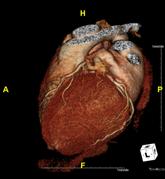

Das Klinikum Ludwigshafen verfügt über einen Kardio-CT der neuesten Generation: Das 128-Zeilen-Gerät ermöglicht eine äußerst präzise Untersuchungsmethode zur Darstellung der Herzkranzgefäße des schlagenden Herzens.

Die koronare Herzerkrankung (KHK) ist eine der häufigsten Erkrankungen in der westlichen Welt. Bei dieser Erkrankung führen Kalkablagerungen an der Gefäßwand (Arteriosklerose) zur Verengung des betroffenen Gefäßes. Diese Engstellen (Stenosen) vermindern die Blutversorgung des Herzmuskels. Kommt es mit dem Fortschreiten der KHK zum Gefäßverschluss, entsteht ein Herzinfarkt.

Die Computertomografie des Herzens (Kardio-CT) ist eine Methode, die frühen Stadien der KHK zu erkennen, bzw. eine KHK mit an Sicherheit grenzender Wahrscheinlichkeit ausschließen zu können.

Prinzipiell ist die Kardio-CT eine Computertomografie (CT), also eine Röntgenuntersuchung, bei der die Röntgenröhre spiralartig um den Patient rotiert. Das Besondere ist die enorme Leistungsfähigkeit der CT, bei der mehrere, sehr dünne Schichten pro Umdrehung gleichzeitig aufgenommen werden.

In Ludwigshafen verwenden wir einen CT der neuesten Generation der Firma Siemens, mit dem wir 128 Schichten pro Umdrehung aufnehmen. Auf diese Weise lässt sich das gesamte Herz mit nur vier bis fünf Umdrehungen erfassen. Für Sie bedeutet das, dass wir Ihre Herzkranzgefäße in der derzeit bestmöglichen Auflösung und mit geringst möglicher Strahlenbelastung darstellen können.